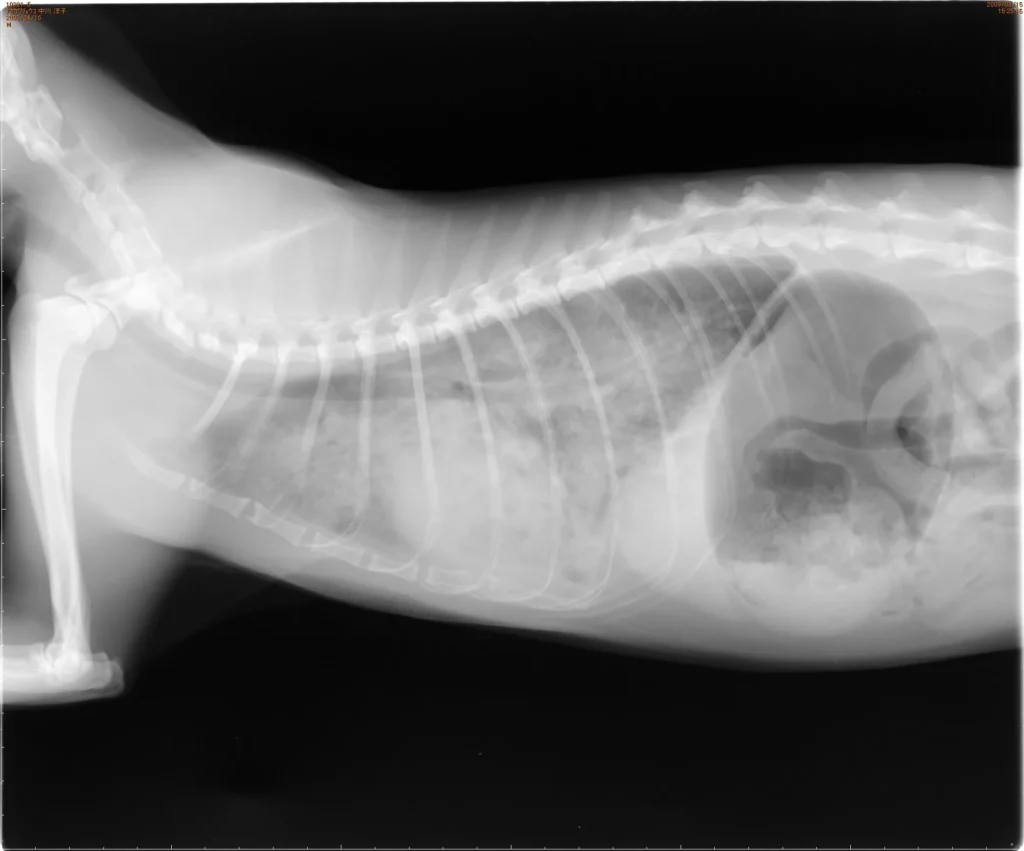

症状がここまで明らかでなくても、「呼吸がおかしい」と感じた時点で早めに動物病院に相談することが大切です。休息時にも呼吸が荒い、少し動いただけで息切れする、咳がなかなか止まらない、ぐったりして横になれない、などの症状が見られたら迷わず受診してください。肺水腫は初期段階では飼い主さんが気付きにくいこともありますが、「いつもと違う」と感じたら早めに診察を受けておくことで、結果的に愛犬の命を守ることにつながります。犬の肺水腫の検査と診断の流れを教えてください動物病院では身体検査に加えて胸部レントゲン検査を行い、肺に水が溜まっていないか確認します。必要に応じて胸部の超音波検査で肺水腫の所見や心臓病の有無を詳しく調べます。また血液検査で全身の炎症や脱水、腎臓の状態などを確認し、安全に治療できるか評価します。犬の肺水腫ではどのような治療が行われますか?治療ではまず酸素投与と利尿剤の投与によって肺水腫を改善します。必要に応じて強心薬や血管拡張薬を用いて心臓の働きと血流を補助します。肺水腫が落ち着いた後は、原因となった心臓の病気に対する治療を続けます。心臓以外が原因の場合も、それぞれの原因に応じた治療と酸素吸入などの治療を行います。肺水腫にかかっている犬のケア方法を教えてください自宅療養中はできるだけ犬を安静にさせ、興奮や激しい運動を避けましょう。退院後も心臓の薬や利尿剤を指示どおりに与えてください。毎日、安静時の呼吸数を測る習慣をつけ、普段より呼吸が速くなるなど異常があればすぐ主治医に相談しましょう。また肥満にならないよう体重管理に気を配り、塩分を控えるなど心臓に負担をかけない生活を心がけることも大切です。